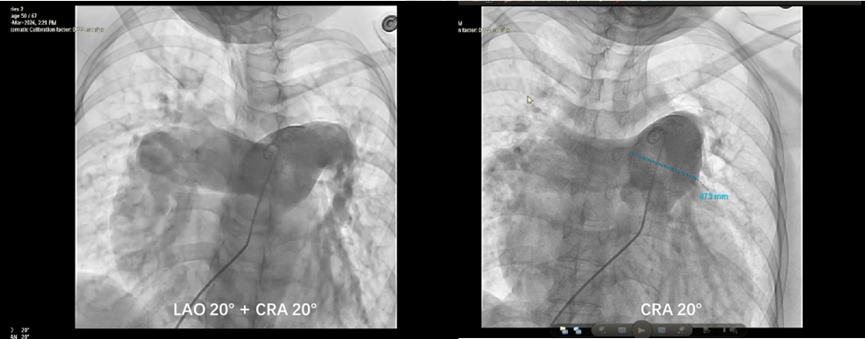

患者为35岁女性,诊断特发性肺动脉高压10余年,既往接受多联靶向药物治疗,病情仍缓慢进展。术前心超显示重度肺动脉高压(估测肺动脉收缩压达145mmHg)、右心显著扩大、中度三尖瓣返流;经右心导管检查测得肺动脉压力(PAP)高达164/43/82mmHg,肺血管阻力(PVR)显著升高(肺总阻力15.94 Wood),提示右心后负荷持续加重。

经团队评估,决定行PADN手术。术中行肺动脉造,确认消融靶点位置并测得肺动脉直径为47.3mm,选择50mm的消融导管。